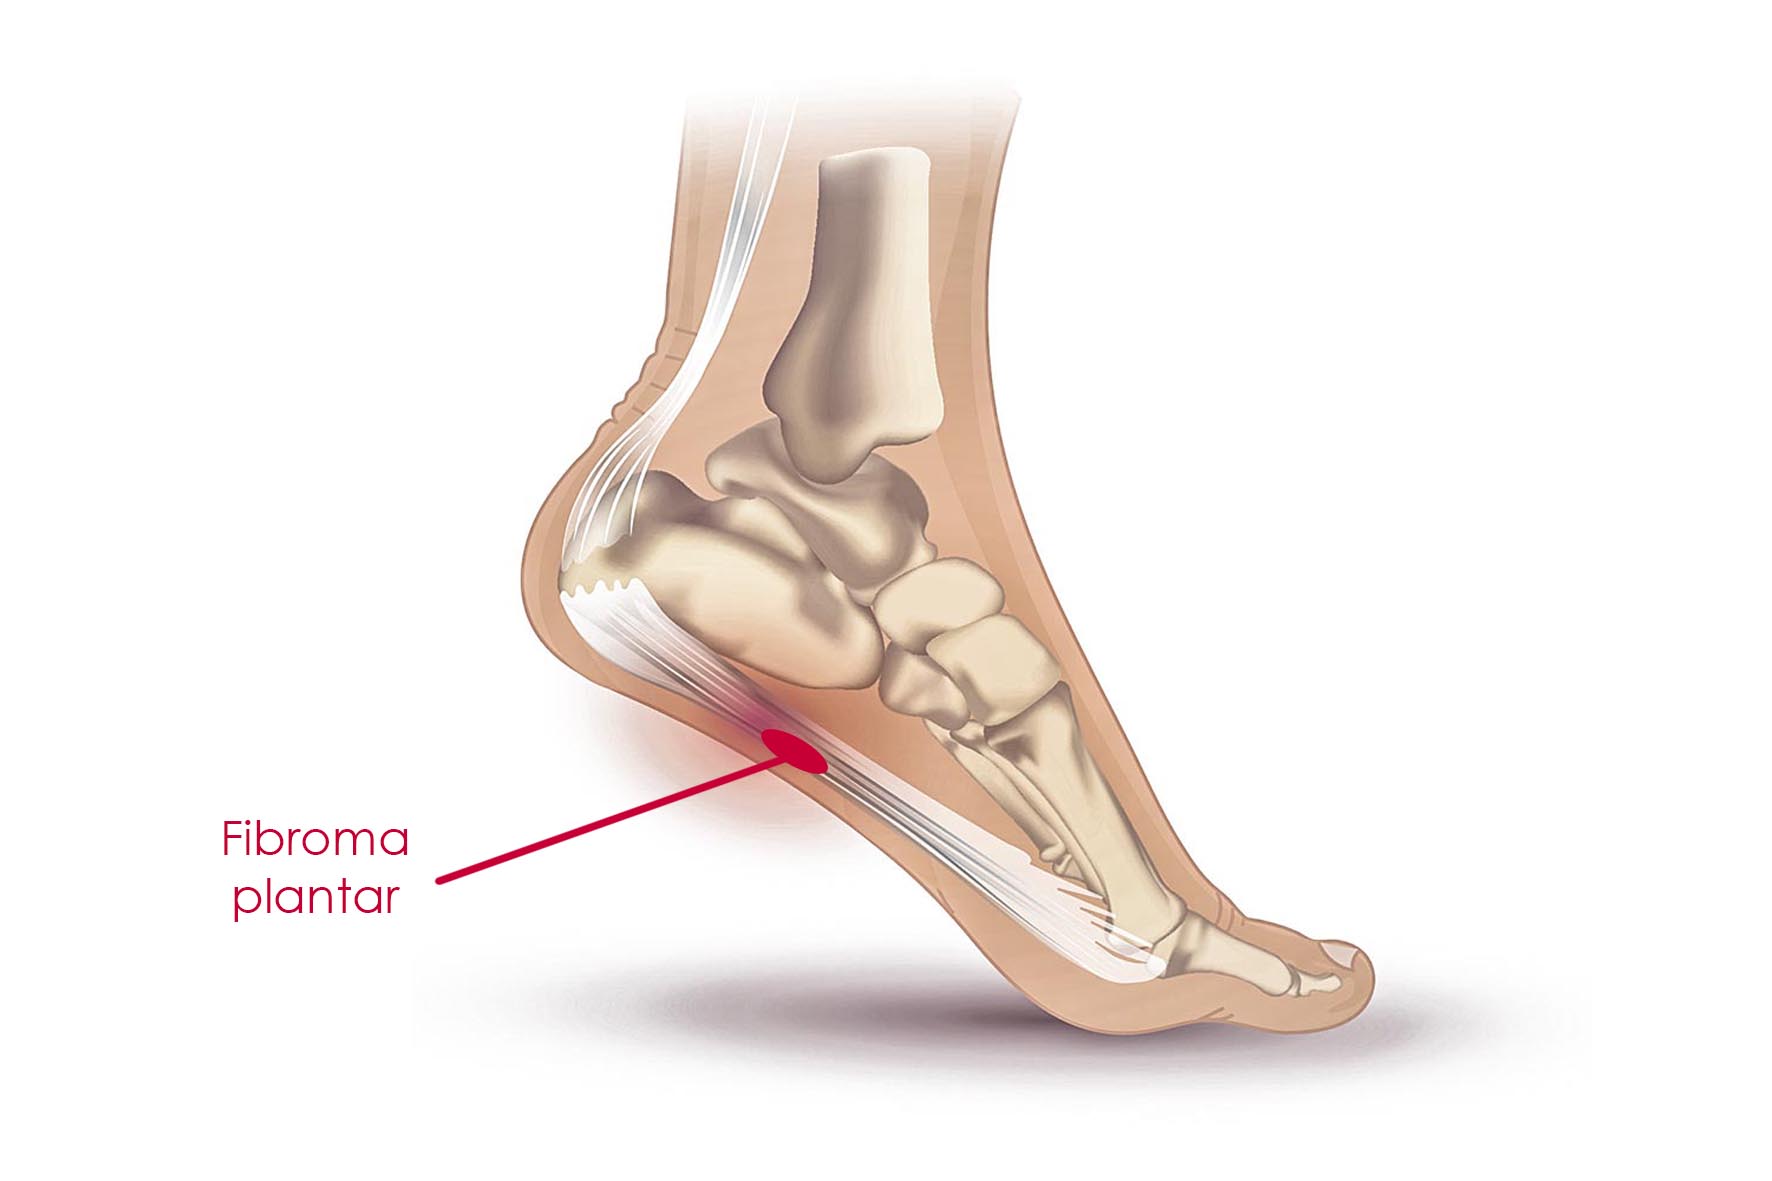

Un fibroma plantar es un nódulo benigno que crece a lo largo de la fascia plantar, localizado con frecuencia en la banda medial. Generalmente tiene un crecimiento lento y mide menos de dos centímetros.

Los síntomas del fibroma plantar consisten en una masa dolorosa en la parte inferior del pie, aproximadamente en el medio del arco plantar entre la almohadilla del talón y la zona anterior del pie. La masa produce una convexidad blanda en el contorno de la parte inferior del pie que puede ser dolorosa si se usa calzado o se la presiona al caminar.

Los fibromas plantares residen en la fascia profunda del pie, entre la piel y las primeras capas (superficiales) del músculo. El estado más agresivo de la fibromatosis plantar puede incluir la piel y las capas de músculos; además, puede envolver los nervios y arterias digitales de la zona.